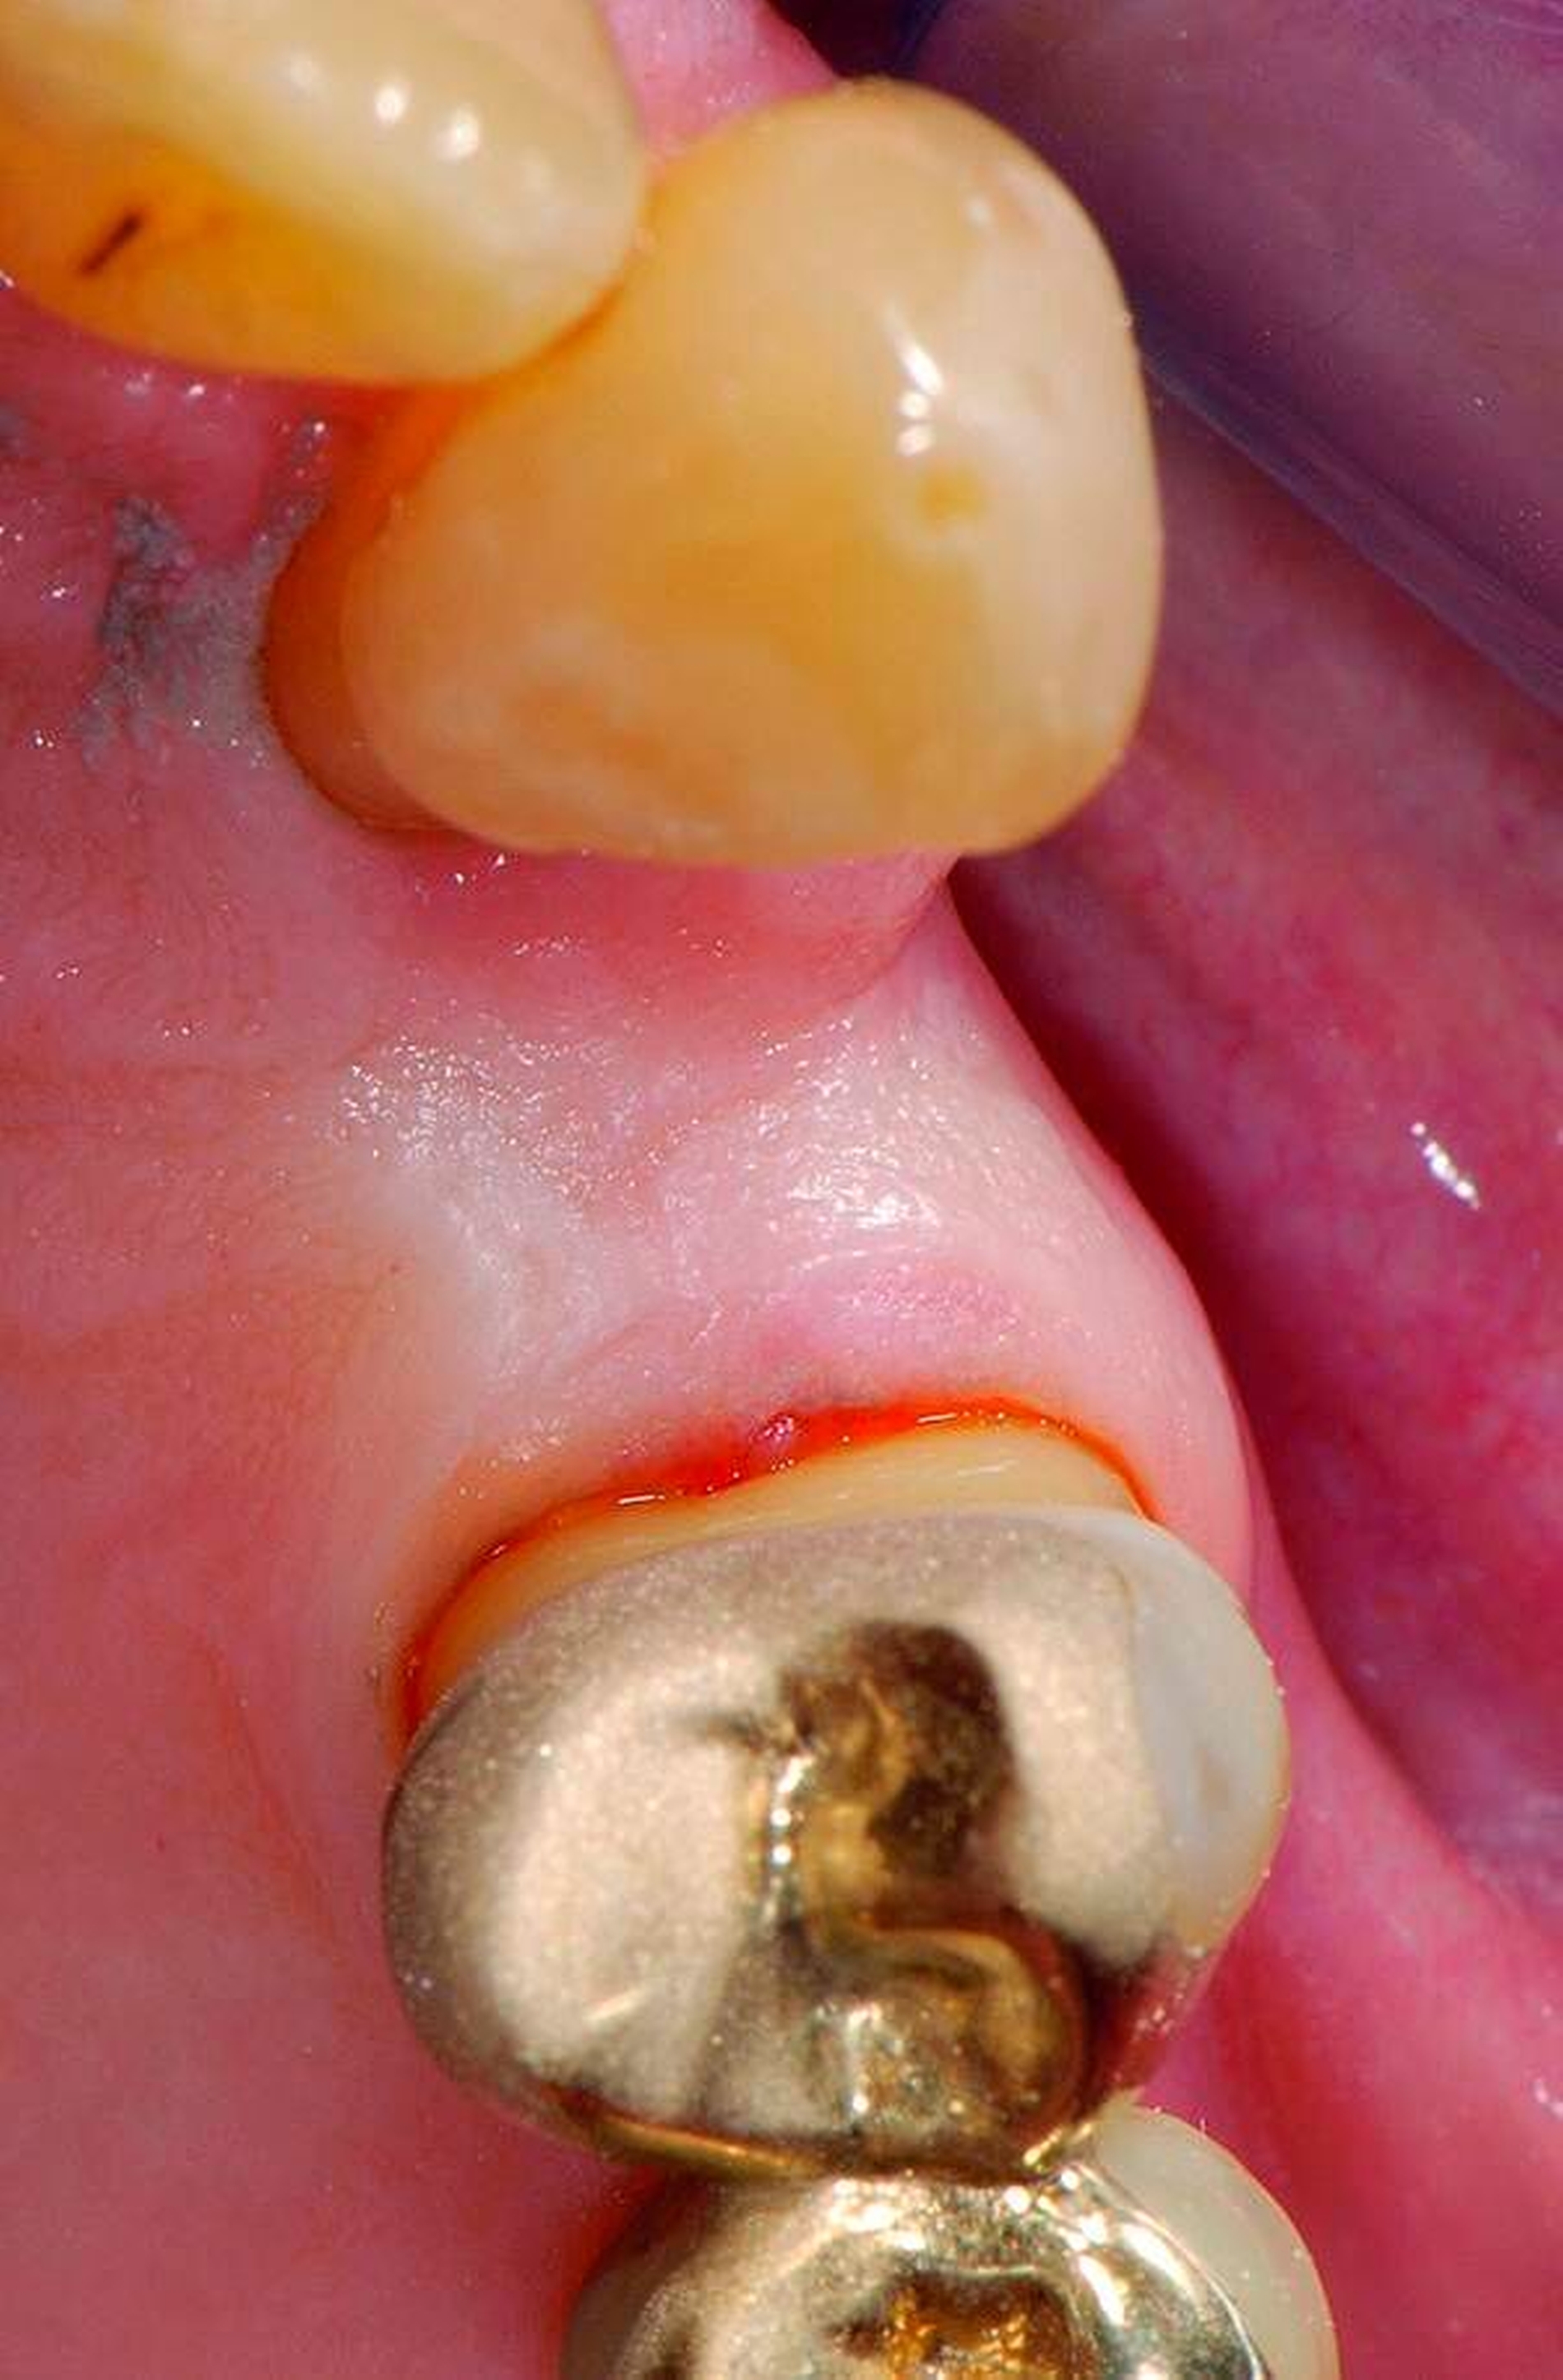

Abbildung 3: ausgedehnte Kronen- und Wurzelkaries unter einer Krone am Pfeilerzahn 47 einer seit Jahrzehnten eingegliederten Brücke von 45–47 bei einer 71-jährigen Patientin, die nach einer zerebrovaskulären Erkrankung unter Antikoagulantientherapie steht, vor etwa zwei Jahren hat sie eine Umstellung auf eine fluoridfreie Zahnpaste vorgenommen.

3. Restaurative Versorgungen bei Wurzelkaries

Freiliegende Wurzeloberflächen können im Alter ein locus minoris resistentiae für Karies sein. Im Zusammenspiel ungünstiger Ernährungsgewohnheiten, nachlassender Mundhygiene sowie Änderungen von Speichelquantität und -qualität kommt es zuweilen zu einem präventiv und restaurativ schwer beherrschbaren Auftreten von Wurzelkaries. Gut zugängliche Kariesläsionen können mit einphasig eingebrachtem Komposit (R1-Restaurationen) angegangen werden (Abbildungen 3 bis 5). Bei schwerer zugänglichen Arealen kommt ein zweiphasiges Vorgehen in Betracht (R2-Restaurationen). Das Vorgehen bei der R1- und bei der R2-Technik wurde mehrfach beschrieben [Frese et al., 2014a, b, c, d; Staehle et al., 2014, 2017]. Im Fall von zirkulärer Wurzelkaries sollte frühzeitig eingegriffen werden, da ansonsten die gesamte Zahnkrone frakturieren kann.